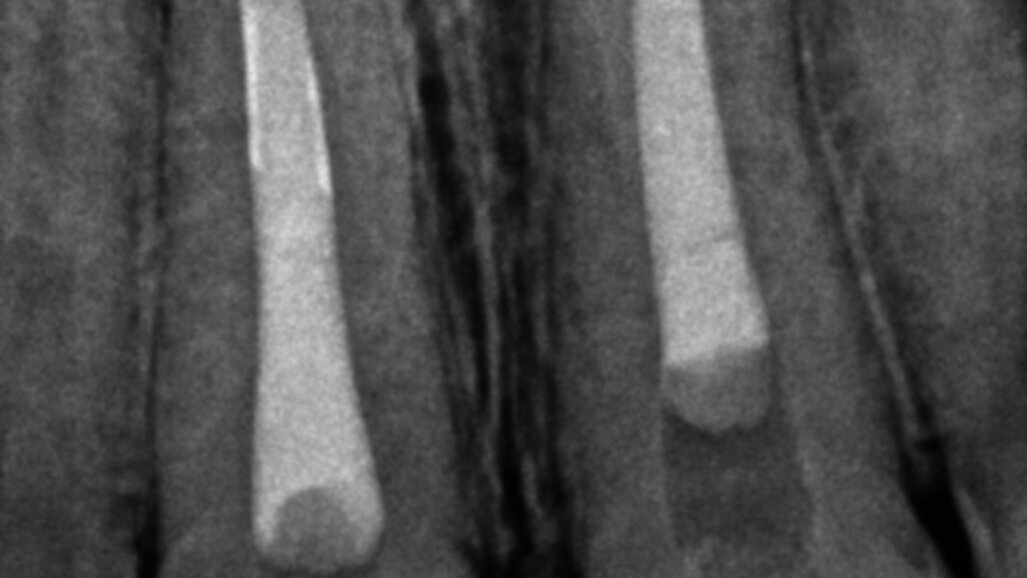

I suctioned the sodium hypochlorite, checked the working length with a paper point and then obturated the canal with a of 3 mm in thickness plug of bioactive cement. I then took a radiograph before obturating the rest of the canal with warm gutta-percha. I used a compomer as a temporary filling material.

The symptoms resolved, so I conducted the second treatment only after some months, when the tooth #11 became tender. Tooth #21 had healed. I performed the same procedure and obtained the same outcome (the four-month follow-up radiograph showed healing).